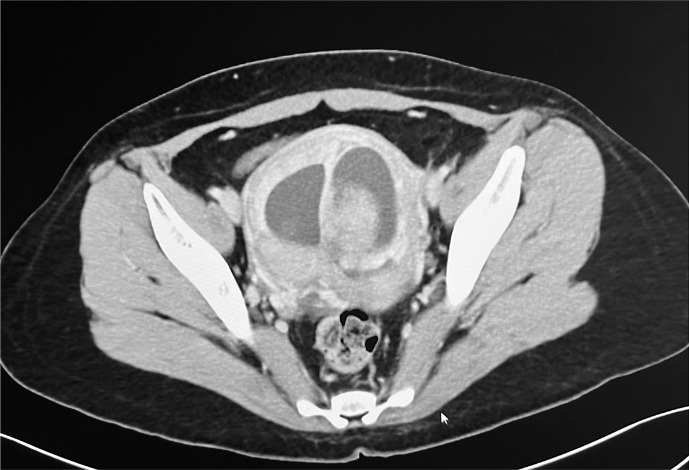

Case presentation: We report a case of a 38-year-old BRCA2-positive breast cancer patient who experienced an unexpected twin pregnancy while undergoing treatment with tamoxifen and olaparib. The patient had been amenorrheic since initiating chemotherapy for more than 600 days and had not received contraceptive counseling. The pregnancy was discovered during routine follow-up imaging computed tomography. After thorough counseling regarding the teratogenic potential of her treatments and radiation exposure, and considering the patient's strong desire to prioritize her own treatment to safeguard her existing three children, the pregnancy was terminated.